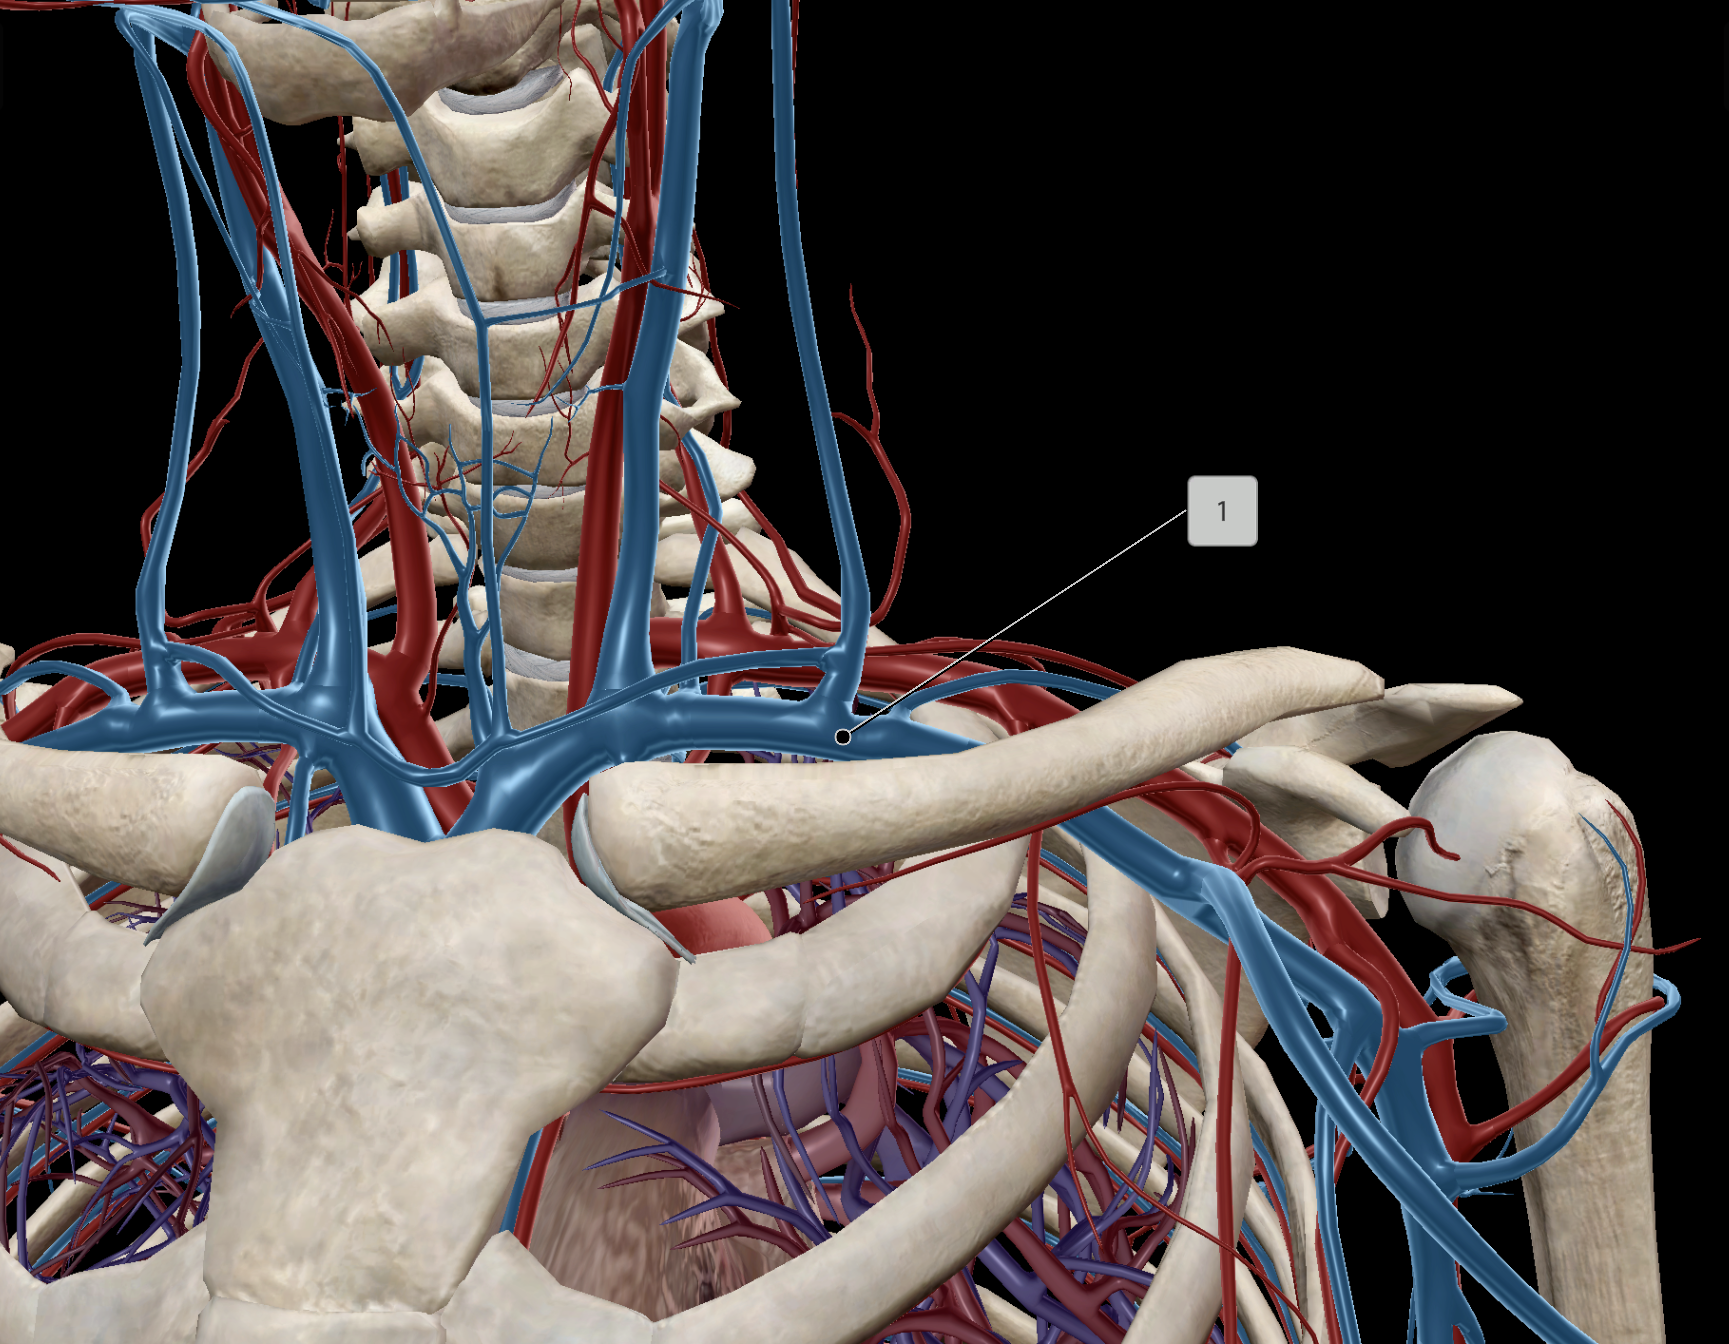

Subclavian Vein

Brachiocephalic Vein

Subclavian Artery

Axillary Vein